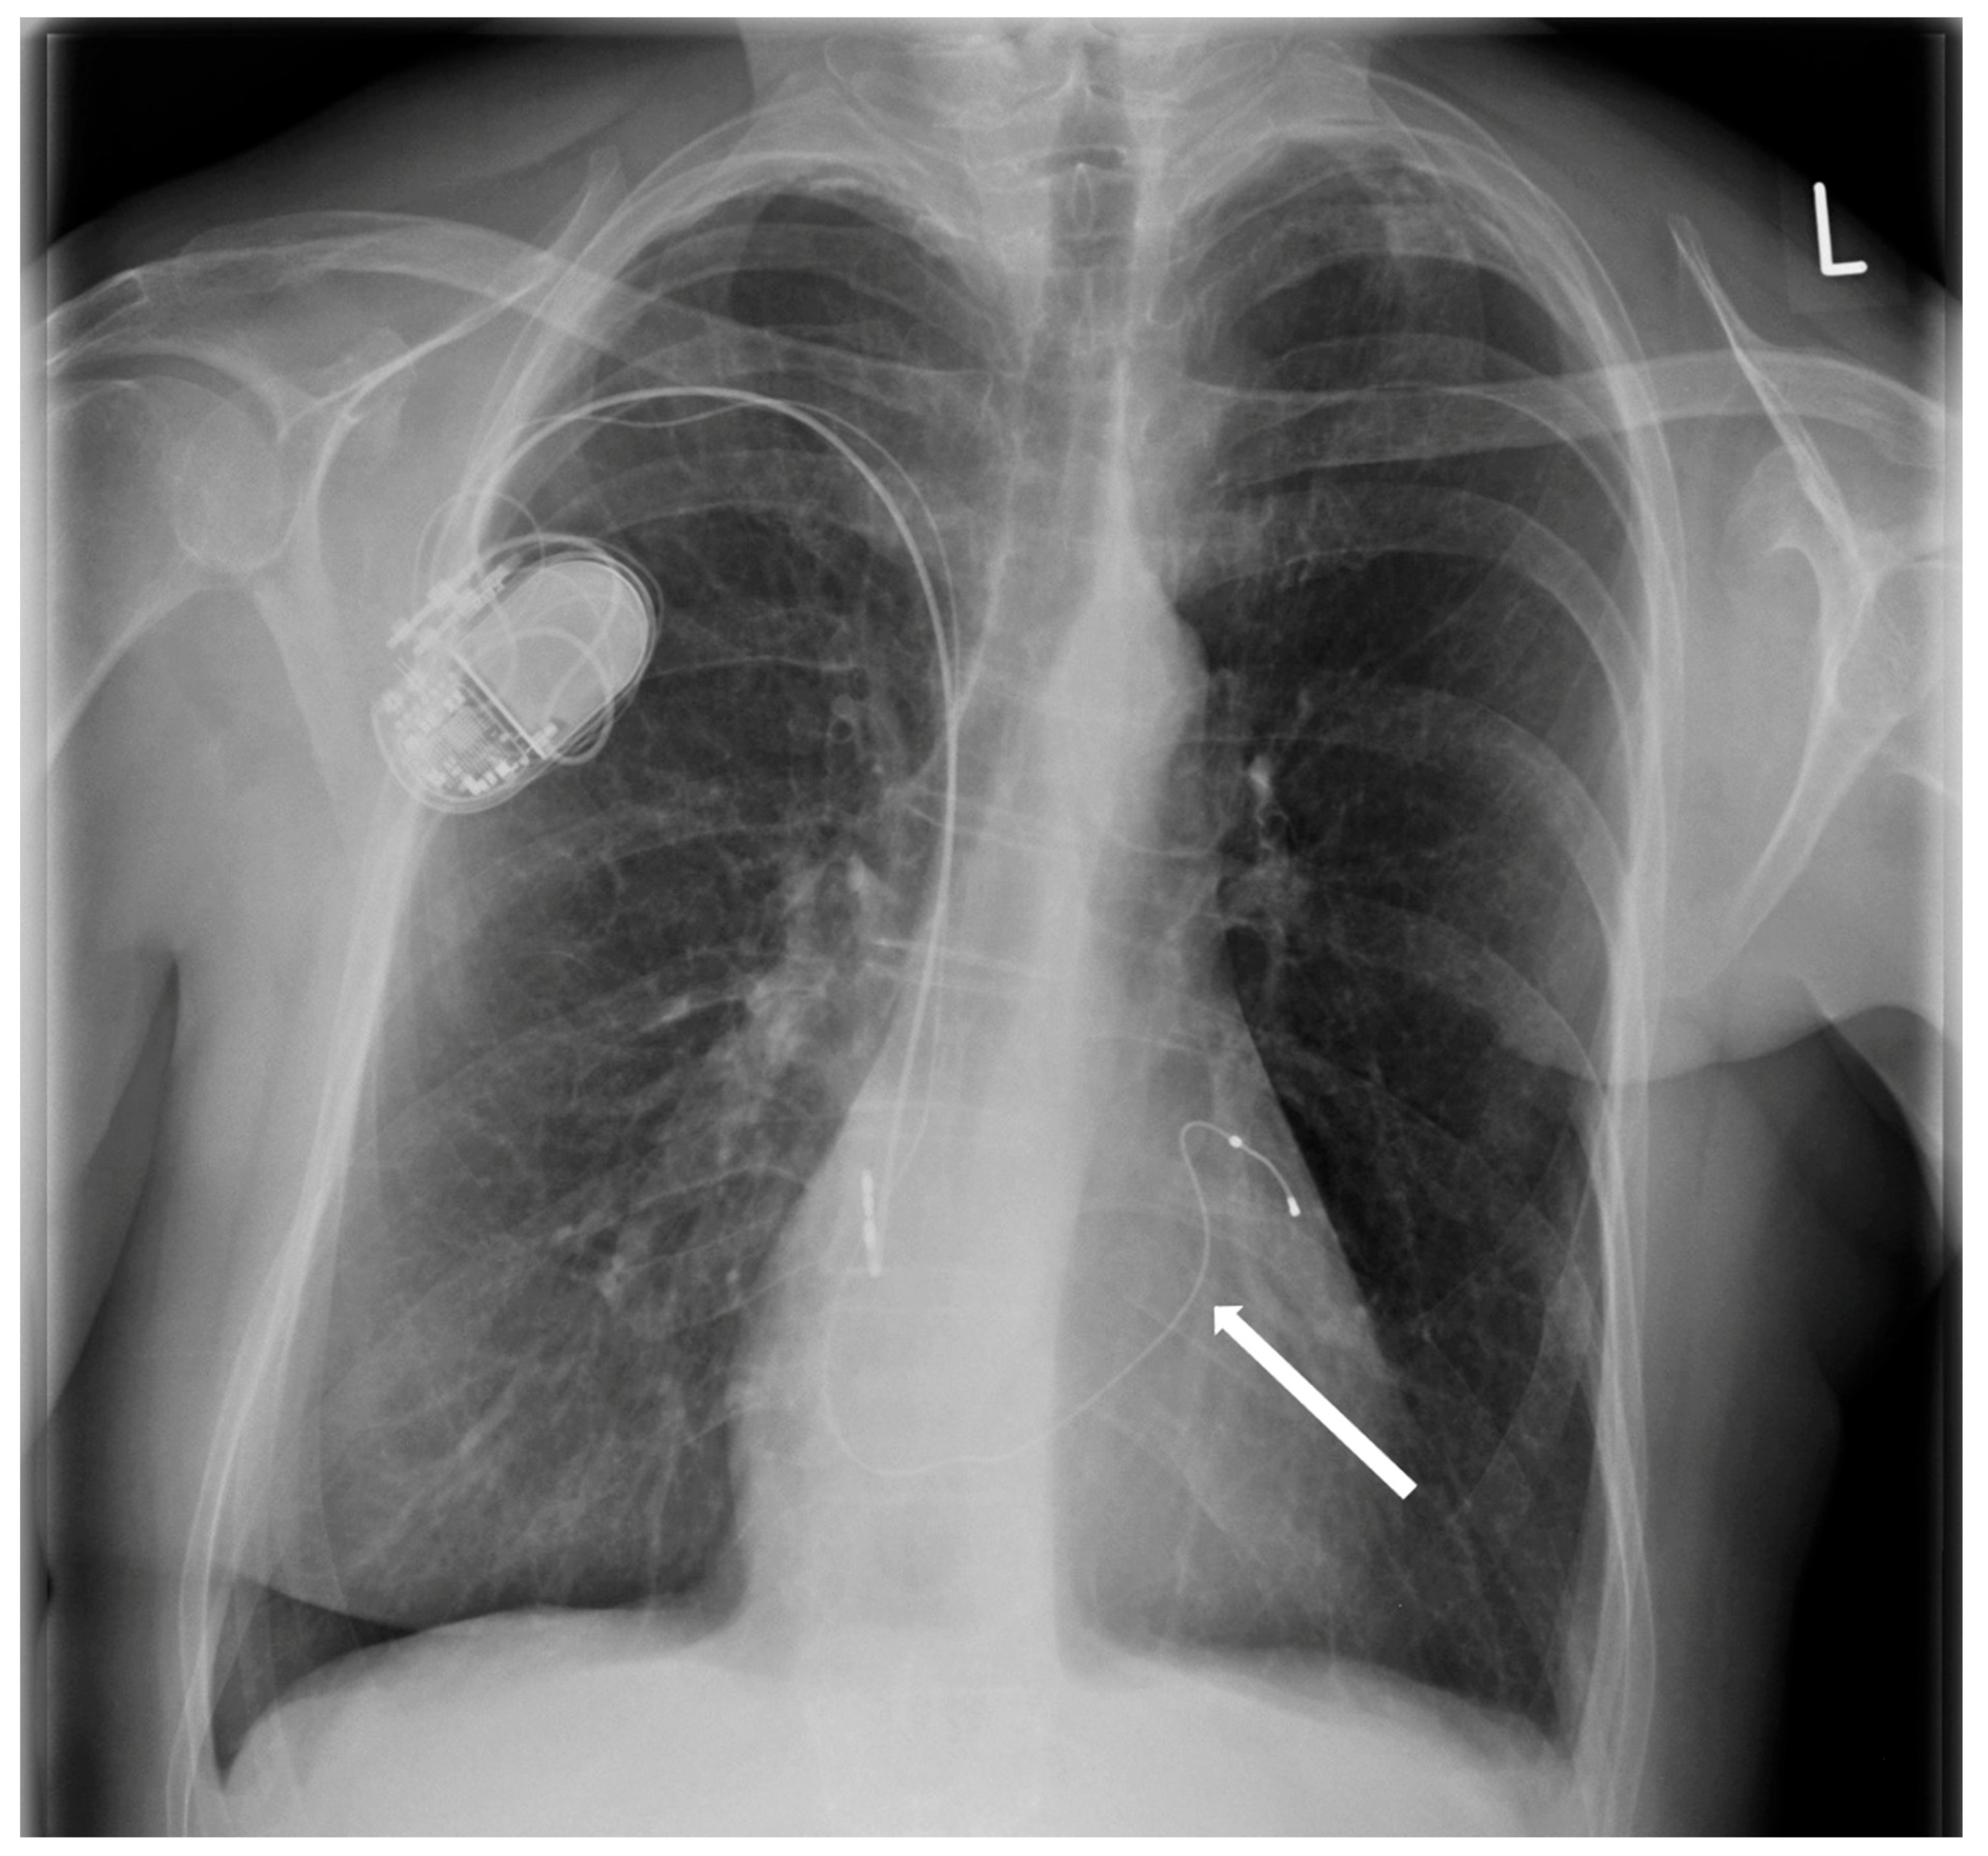

After one month, during a follow-up hospitalization, the patient was still on diuretic treatment. Symptoms of right ventricular failure were still present, although less severe. Echocardiography still showed tricuspid regurgitation and restrictive positioning of the septal leaflet of the tricuspid valve. Pacemaker control revealed 53% atrial pacing and 6% right ventricular pacing. Due to the small percentage of right ventricle pacing, the remaining functional right ventricular lead was transvenously removed, and a new lead was implanted into the coronary sinus (Figure 6). A pacemaker check confirmed optimal pacing of the atrium and coronary sinus. In a 4-month follow-up, we observed a decrease in tricuspid valve regurgitation, allowing for the discontinuation of diuretics. The patient has not manifested cardiac failure exacerbations over the past six months.

Figure 6. Chest X-ray after removal of the RV electrode and implantation of the electrode into the coronary sinus (arrow).